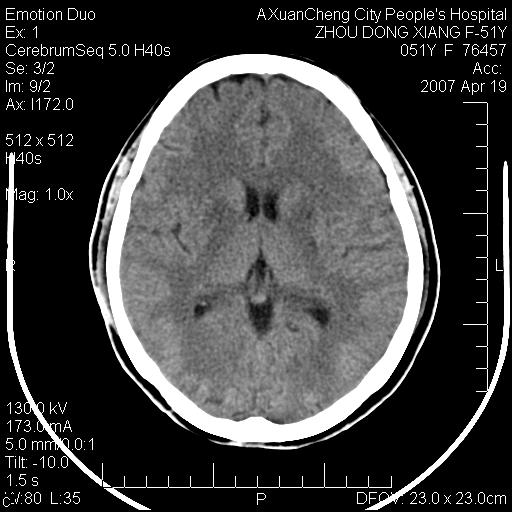

这个患者是外科手术后,第一次ct检查显示颅内多发积气和椎管内积气

现在复查后颅内这样怎么会事

双侧苍白球区见片状对称性低密度影 多考虑 缺氧引起的

第一次ct检查显示颅内多发积气和椎管内积气,现双侧基底节区及四叠体池周围多发斑片状低密度影,灰白质分界清楚,侧脑室前角变窄,患者为胆囊手术后,现在患者好象已经多脏器衰竭表现了,考虑:1. 血源性脑脓肿脑炎期改变?2. 缺血缺氧性改变?

第一次ct检查显示颅内多发积气和椎管内积气,现双侧基底节区及四叠体池周围多发斑片状低密度影,灰白质分界清楚,侧脑室前角变窄,患者为胆囊手术后,现在患者好象已经多脏器衰竭表现了,考虑:1. 血源性脑脓肿脑炎期改变?2. 缺血缺氧性改变?--支持